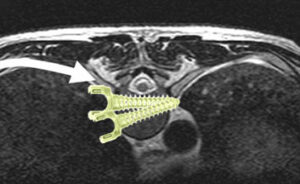

矯正に使用する機械は主に椎弓根スクリューとロッドを使用します。時によってはフックやワイヤーも使用します。(図5)

椎弓根にスクリューを設置し、そこにロッドを連結させて様々なテクニックを用いてカーブを矯正していきます。(図6)